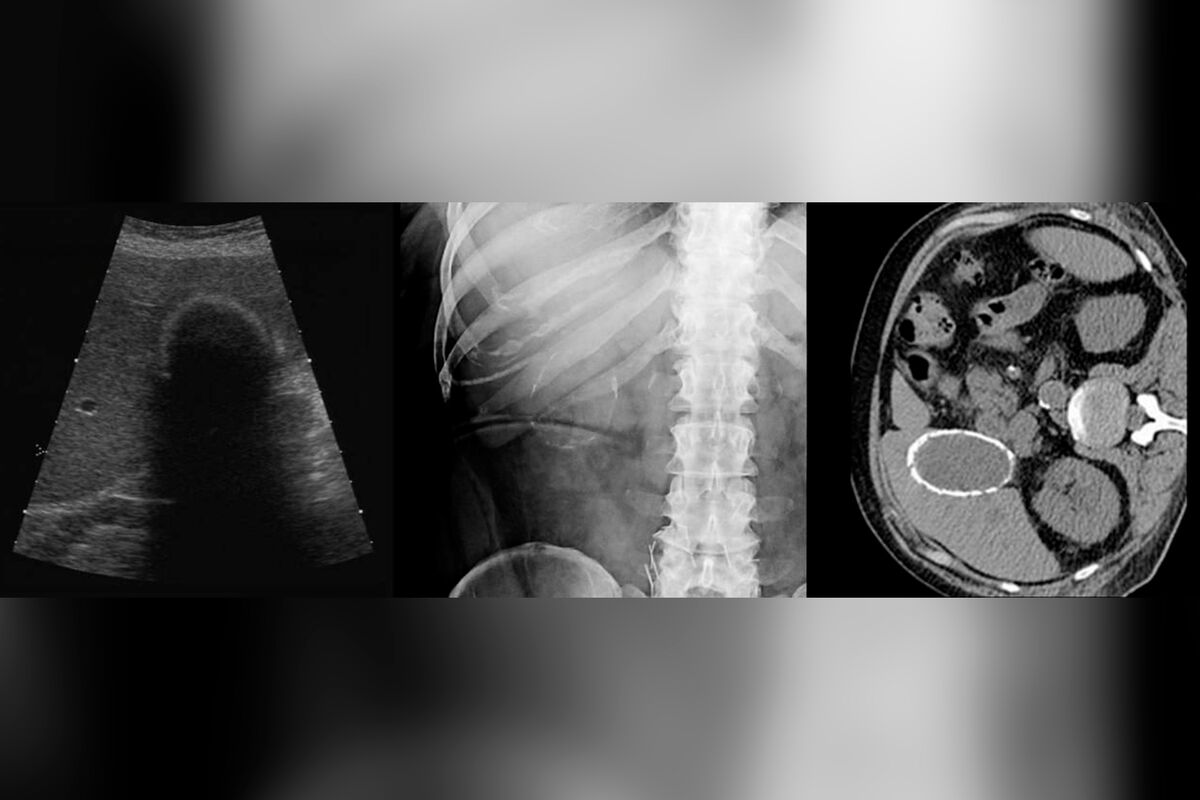

Врачи городской больницы Реутова прооперировали местную жительницу с редкой патологией — «фарфоровым» желчным пузырем. Об этом сообщили в пресс-службе минздрава Московской области.

Женщина обратилась с жалобами на тяжесть в правом подреберье. Ей диагностировали редкую разновидность калькулезного холецистита, когда стенки пузыря покрываются слоем кальция, делая орган твердым.

Пациентке провели малоинвазивную операцию, удалив желчный пузырь через небольшие проколы.

«Сам пузырь настолько затвердел, что его было почти невозможно разрезать скальпелем», — поделились медики.